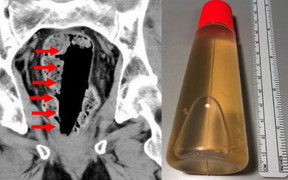

Người vợ sợ run khi phát hiện chồng mình bất tỉnh trong bồn tắm sau khi ông cố gắng chữa chứng táo bón bằng cách nhét nguyên một lọ keo hình trụ vào trực tràng.